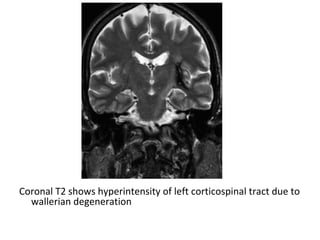

10-Wallerian Degeneration :

c) Radiographic Features :

-Hyperintensity on T2-weighted images along the affected tracts

-Conventional MRI depict WD when sufficiently large bundles of

fibers are involved along the corticospinal tract , the corpus

callosum , fibers of the optic radiations , fornices and

cerebellar peduncles

-The most common observations regard the corticospinal tract

-WD of cerebellar peduncles is rarely described , It usually

involves the middle ones because they are largest and the

main path for pontocerebellar tracts

-Shows diffusion restriction

Coronal T2 shows hyperintensity of left corticospinal tract due to

wallerian degeneration